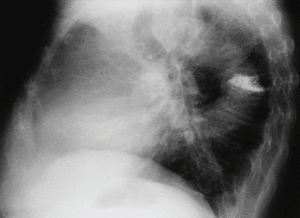

En la radiografía posteroanterior y lateral de tórax observamos como hallazgo más significativo una disminución de la altura y aumento de densidad de un cuerpo vertebral dorsal medio.

Fig. 1.

En esta paciente, coincidiendo con el dolor, se realiza radiografía dorsal donde se aprecia aplastamiento D5-D8. Posteriormente en la resonancia magnética se demuestra fractura y aplastamiento reciente de D7 en probable relación con la osteoporosis que presenta. Se le realizó una vertebroplastia mejorando clínicamente en el plazo de varios días.